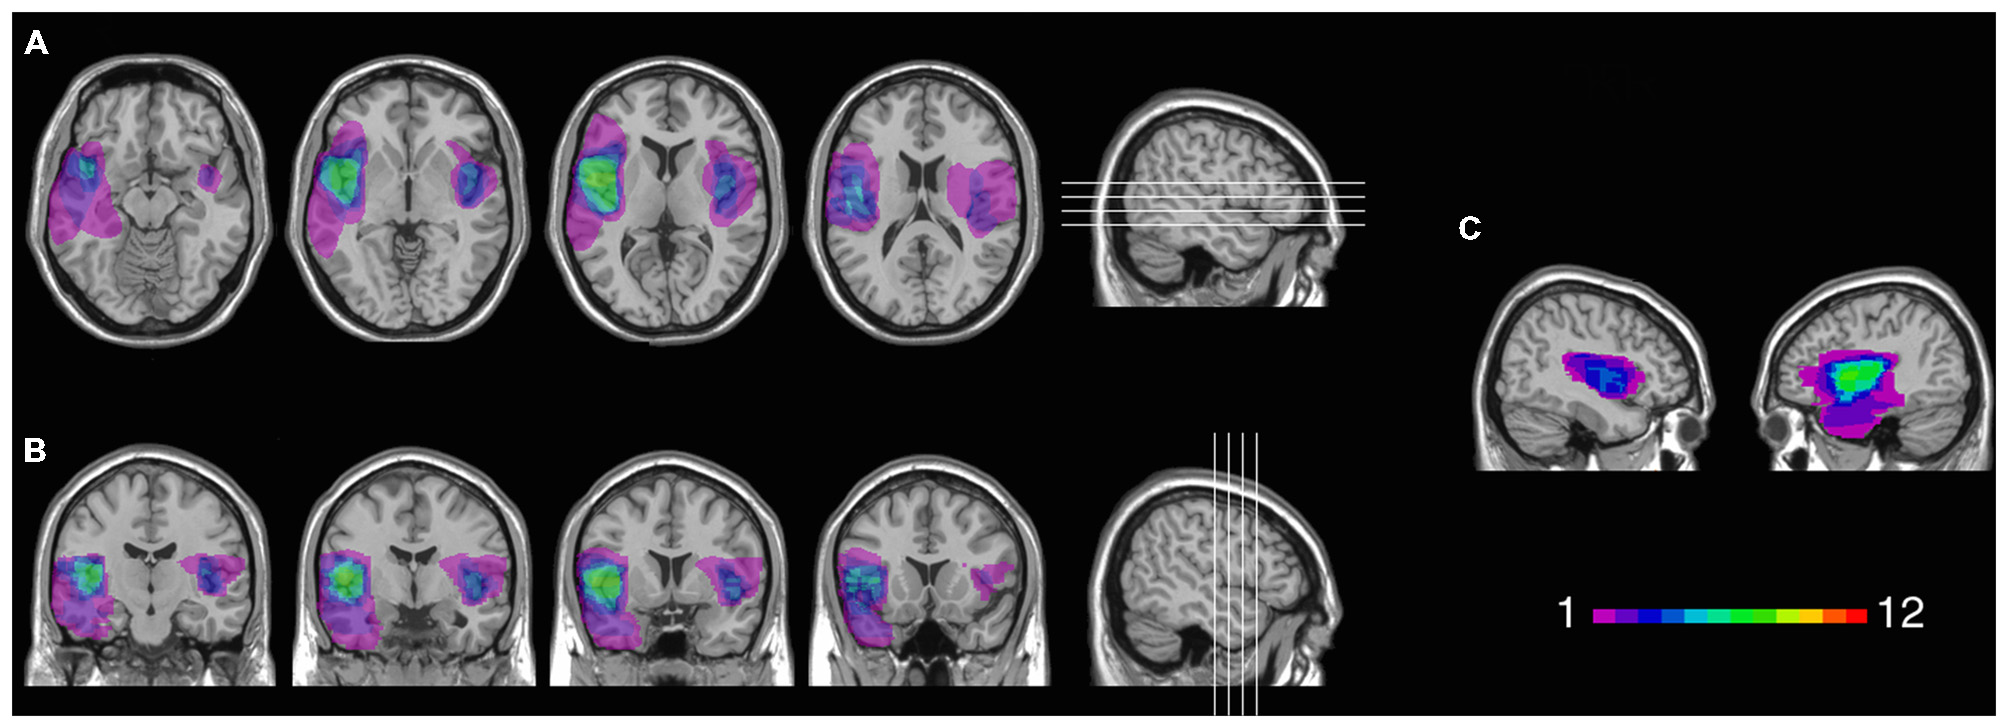

Twelve patients (5 females) had lesions involving the insular cortex, hidden in the lateral sulcus, covered by frontal, temporal, and parietal opercula, as well as surrounding gray and white matter (see Figure 1). Since lesions predominantly involved the insular cortex (see “Results” Section), we henceforth refer to this group as “Insular patients”. Lesions were caused by an ischemic or hemorrhagic stroke of the middle cerebral artery (MCA) and were unilateral in all cases (left hemisphere: 8 cases, right hemisphere: 4 cases). Thirteen patients (7 females) had brain damage that spared the insular cortex in both hemispheres (see Figure 2). We henceforth refer to this group as “Non-insular patients”. Lesions were caused by ischemic or hemorrhagic stroke (9 cases) or tumor resection (4 cases), were unilateral in all cases (left hemisphere: 7 cases, right hemisphere: 6 cases), and mainly involved the occipital cortex, the temporal cortex, and the superior frontal cortex. In no case did patients’ lesions involve the mOFC (see Sellitto et al., 2010). There was no significant difference in lesion volume between Insular patients and Non-insular patients (33.33 vs. 25.36 cc.; p = 0.29).

FIGURE 1

Figure 1. Location and overlap of brain lesions in Insular patients. The image shows the lesions of the Insular patients projected on the same four axial slices (A) and on the same four coronal slices (B) of the standard Montreal Neurological Institute (MNI) brain. In each slice, the left hemisphere is on the left side. The level of axial and coronal slices has been marked by white lines on the sagittal view of the brain. Sagittal views of the MNI brain show the degree of lesion coverage for the right- and left-lesioned Insular patients; the color bar indicates the number of overlapping lesions (C).

Figure 1 shows the extent and overlap of brain lesions in Insular patients. As is evident, although all patients had damage that included the insula, areas adjacent to the insula that are within the MCA blood supply territories were damaged to some degree as well. This included parts of the somatosensory cortex, the basal ganglia (e.g., caudate, putamen), the temporal lobe (especially the superior portions), the dorsolateral and/or ventrolateral prefrontal cortex, the inferior parietal lobule, the occipito-parietal junction, and the dorsomedial sectors of the occipital lobe. Lesions of Insular patients overlapped maximally in Brodmann Area (BA 20) (M = 7.0 cc., SD = 11.0 cc.), BA 21 (M = 2.7 cc., SD = 5.5 cc.), BA 38 (M = 2.1 cc., SD = 2.7 cc.), and BA 22 (M = 1.3 cc., SD = 2.2 cc.), as well as not numbered areas (M = 18.1 cc., SD = 6.4 cc.). Since the insular cortex is part of the areas with no Brodmann label (e.g., Kurth et al., 2010), we calculated maximal overlap location also using the Automated Anatomical Labeling (AAL) template (Tzourio-Mazoyer et al., 2002). This included the left (M = 6.6 cc., SD = 2.7 cc.) and the right (M = 6.5 cc., SD = 1.3 cc.) insula, as well as the temporal lobe bilaterally [temporal pole (M = 1.9 cc., SD = 2.4 cc.); superior portions of the temporal lobe (M = 5.2 cc., SD = 3.3 cc.)].